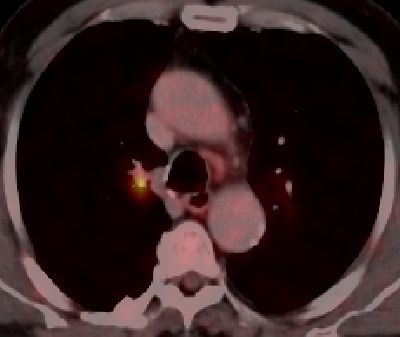

blauer Punkt   56-jähriger Mann mit einem Adeno-Ca des rechten Mittellappens. Im CT große Raumforderung im rechten Hilus. Das PET-CT zeigt, dass der eigentliche Tumor unterhalb der Raumforderung sitzt.